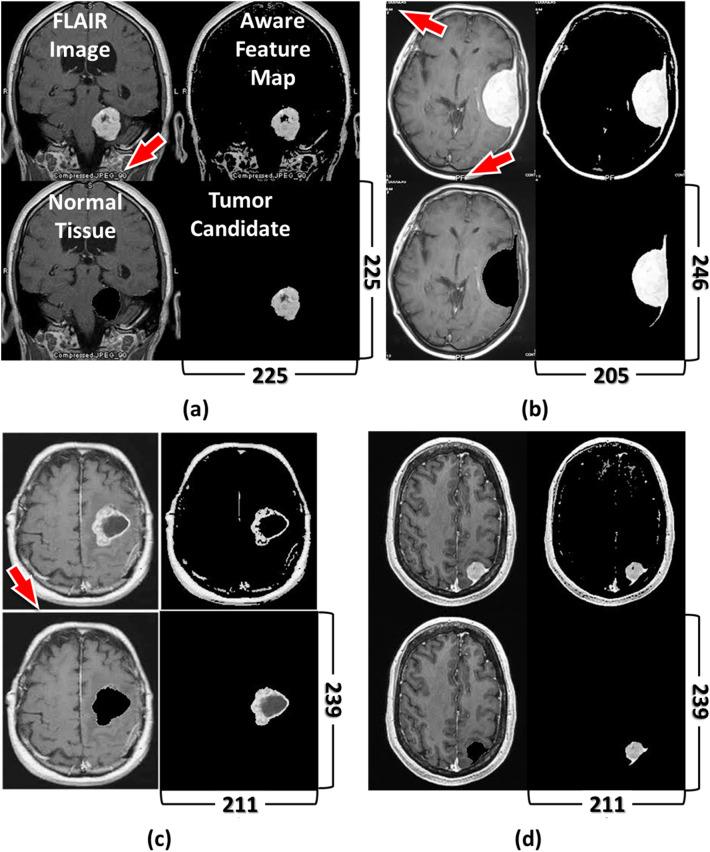

We demonstrate that isomorphically mapping gray-level medical image matrices onto energy spaces underlying the framework of fast data density functional transform (fDDFT) can achieve the unsupervised recognition of lesion morphology. By introducing the architecture of geometric deep learning and metrics of graph neural networks, gridized density functionals of the fDDFT establish an unsupervised feature-aware mechanism with global convolutional kernels to extract the most likely lesion boundaries and produce lesion segmentation. An AutoEncoder-assisted module reduces the computational complexity from [Formula: see text] to [Formula: see text], thus efficiently speeding up global convolutional operations. We validate their performance utilizing various open-access datasets and discuss limitations. The inference time of each object in large three-dimensional datasets is 1.76 s on average. The proposed gridized density functionals have activation capability synergized with gradient ascent operations, hence can be modularized and embedded in pipelines of modern deep neural networks. Algorithms of geometric stability and similarity convergence also raise the accuracy of unsupervised recognition and segmentation of lesion images. Their performance achieves the standard requirement for conventional deep neural networks; the median dice score is higher than 0.75. The experiment shows that the synergy of fDDFT and a naïve neural network improves the training and inference time by 58% and 51%, respectively, and the dice score raises to 0.9415. This advantage facilitates fast computational modeling in interdisciplinary applications and clinical investigation.